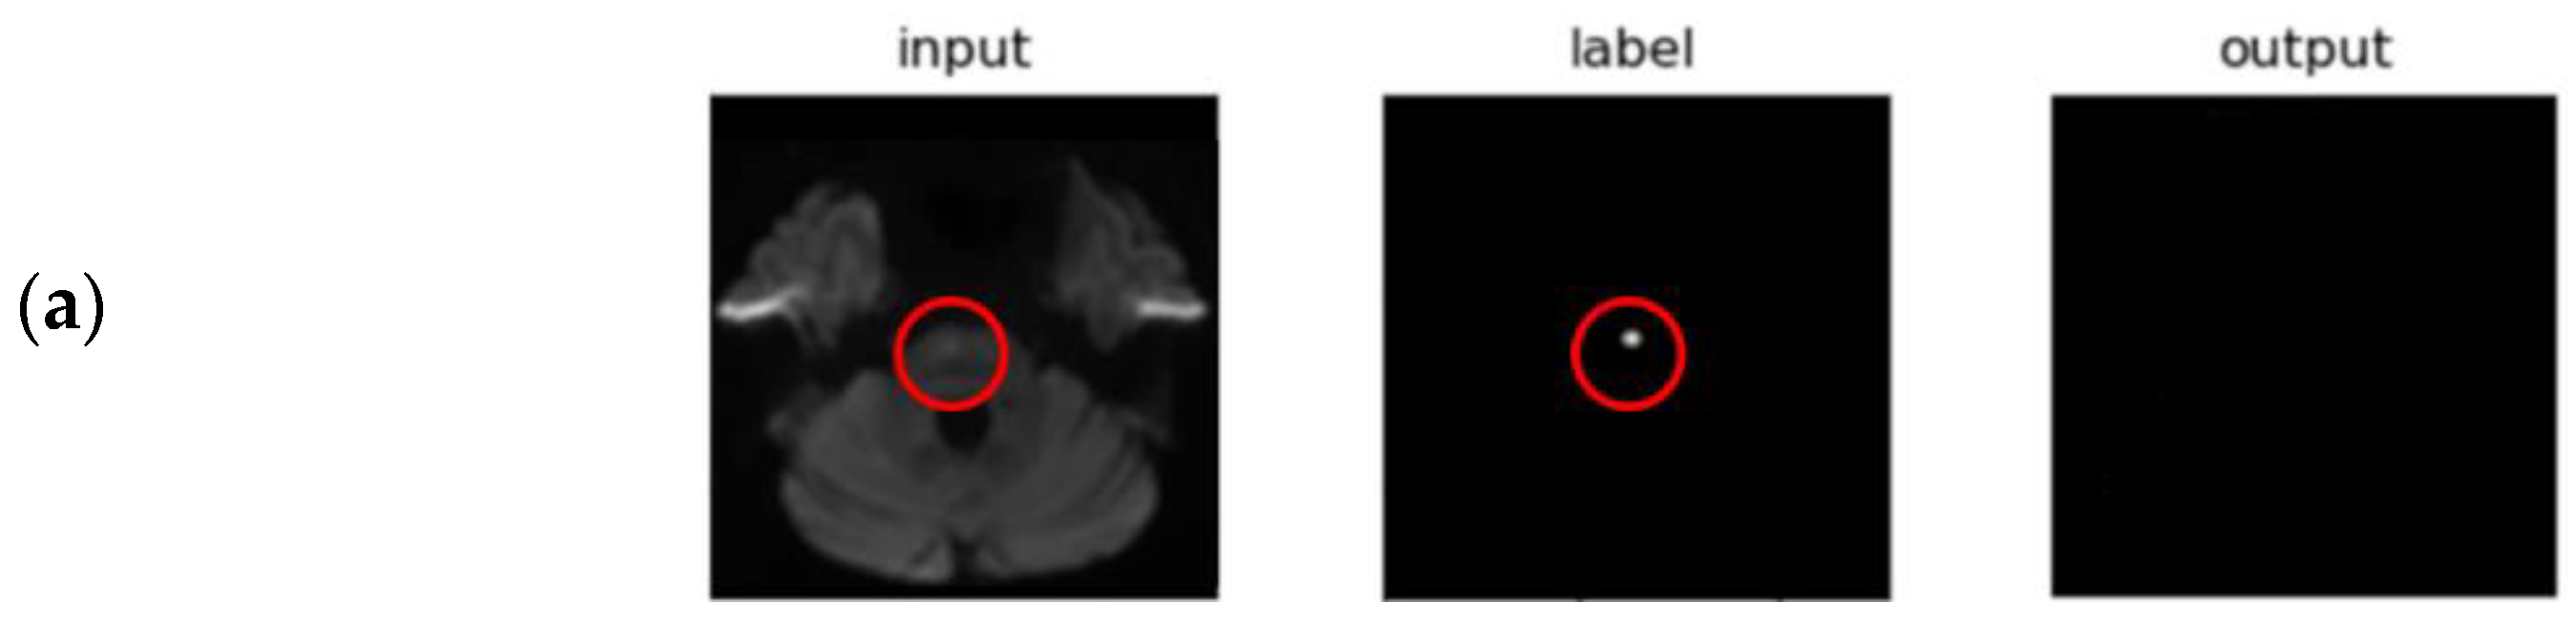

- Indirect Volume Estimation (Using 2D Segmentation)

3.2. Segmentation Performance